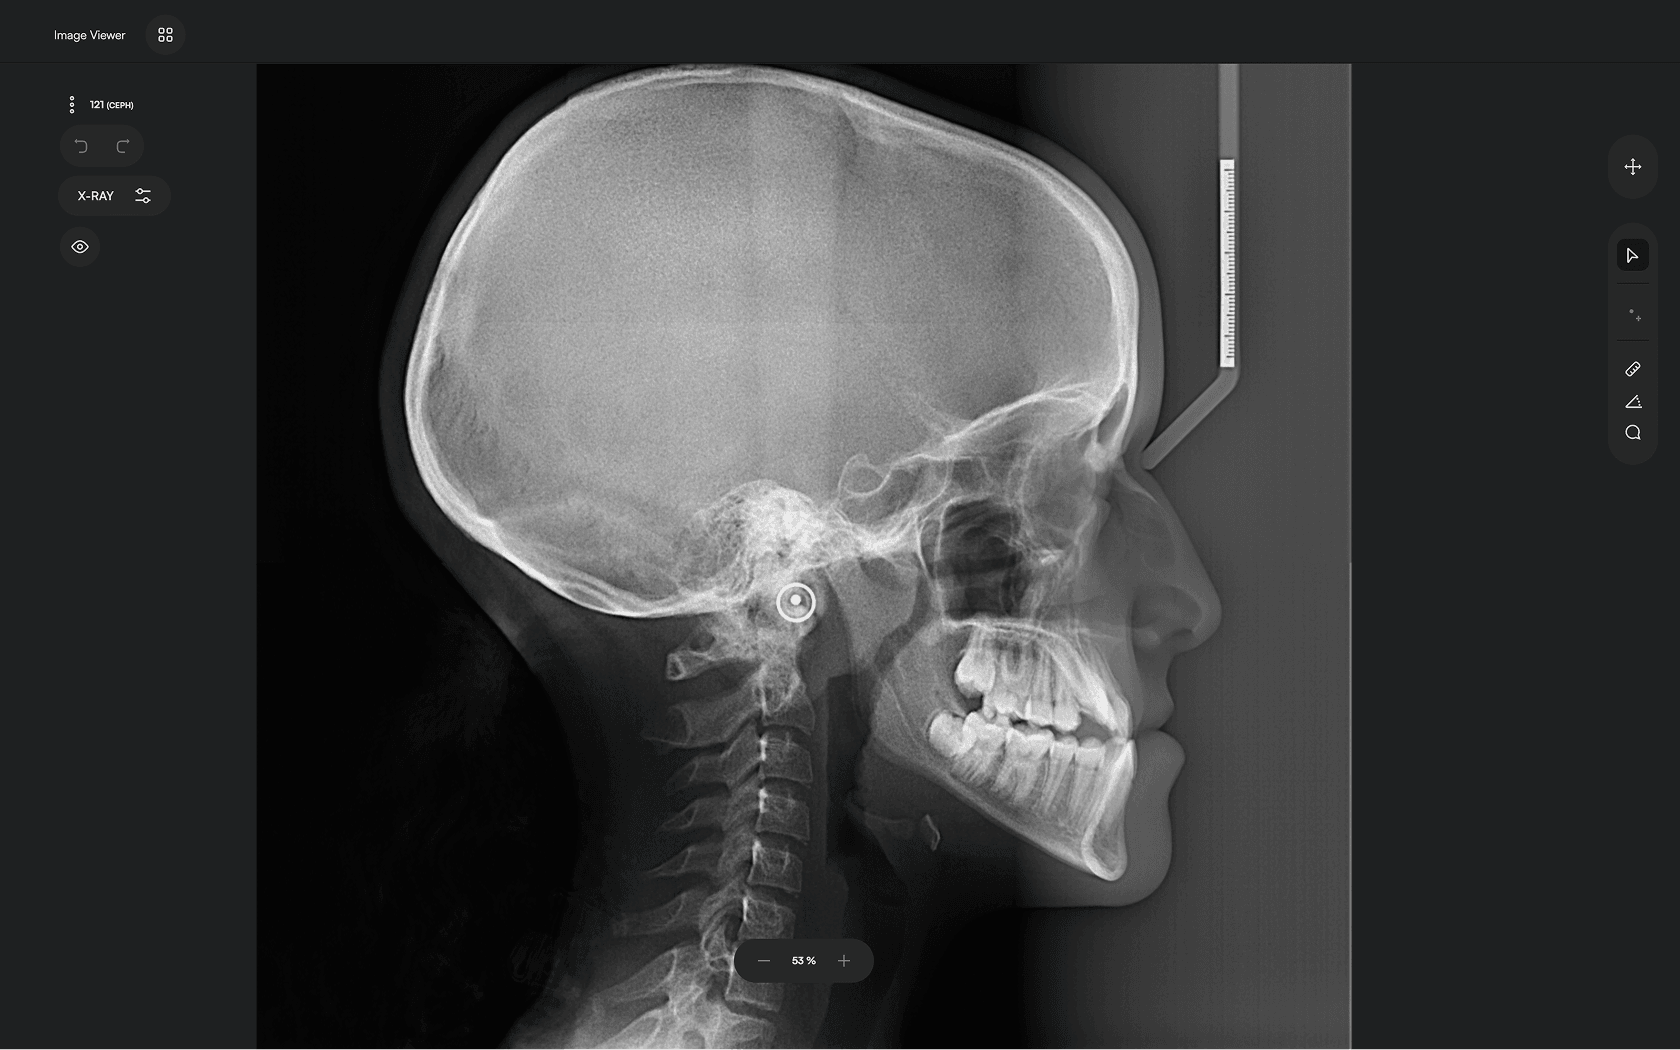

AI-driven Automated Lateral

Cephalometric Tracing

150+ landmarks traced in seconds

Identify 150+ orthodontic landmarks in under 10 seconds — a task that

traditionally may take more than 30 minutes.